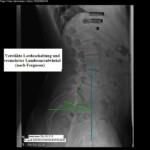

Ἰδιαίτερη ἐπιβάρυνση ὑφίστανται οἱ ἀθλούμενοι σὲ spor, ὅπου προκαλεῖται φόρτιση τῆς Σ.Σ. εὑρισκομένης τῆς τελευταίας σὲ στάση ὑπερεκτάσεως ἢ ὑπερλορδώσεώς, ὅπως συμβαίνει σὲ διάφορα εἴδη χοροῦ, καλλιτεχνικοῦ πατινάζ, ἀκοντισμοῦ, γκόλφ, ἄρσεως βαρῶν (εἰκ.1, 2, 3,4, 5 καὶ 6). Καλὸ εἶναι νὰ μὴν παραβλέπονται προδιαθεσικοὶ παράγοντες ὅπως συγγενεῖς δυσπλασίες στὴν κατασκευὴ τῶν σπονδυλικῶν τόξων (δισχιδὴς ράχις), ὑπερλόρδωση τῆς ΟΜΣΣ μὲ αὐξημένη ὀσφυοϊερὰ γωνία(Ferguson) καὶ μετατόπιση τοῦ κέντρου βάρους ποὺ διέρχεται ἀπὸ τὸν Ο3 πέραν τῆς προσθίας παρυφῆς τοῦ Ι1 (εἰκ. 14). Παιδιὰ μὲ συγγενεῖς 1ου βαθμοῦ ποὺ ἔχουν τέτοιες δυσπλασίες, ἐμφανίζουν ὑψηλότερα ποσοστά προσβολῆς. Στὰ ἀγόρια ἡ νόσος εἶναι 3-4 φορὲς συχνότερη συγκριτικῶς πρὸς τὰ κορίτσια, ἀλλὰ ὅταν ἐμφανιστεῖ στὰ τελευταῖα, προκαλεῖ σοβαρότερα ἐνοχλήματα. Ἡ νόσος ἐνδημεῖ σὲ ὑψηλώτερα ποσοστὰ στοὺς Ἐσκιμώους τῆς Ἀλάσκας.

Ἡ διεθνὴς ταξινόμηση τῶν σταδίων τῆς σπονδυλολισθήσεως ἀκολουθεῖ τὸν ὑποδειχθέντα ὑπὸ τοῦ Meyerding κανόνα, σύμφωνα μὲ τὸν ὁποῖο τὸ μῆκος τῆς ὀλισθήσεως ἑνὸς σπονδύλου εἶναι συνάρτηση τοῦ μήκους τῆς βάσεως τοῦ ὑποκειμένου σπονδυλικοῦ σώματος. Ἡ διάγνωση ἢ ἡ ὑποψία μιᾶς σπονδυλολύσεως καὶ κατὰ τὶς περιστάσεις τῆς σπονδυλολισθήσεως τίθεται μὲ μία πλαγία ἀκτινογραφία ΟΜΣΣ καὶ μὲ ἐπικέντρωση στὸ ὕψος Ο4-Ο5-Ῑ1. Ὀριστικὴ ἐπιβεβαίωση δίδεται διὰ τῆς διενεργείας λοξῆς (45ο) ἀκτινογραφίας, ὅπου ἡ ἀπεικονιζόμενη σπονδυλόλυση περιγράφεται συχνὰ μὲ τὸν ἀποδοθέντα ὑπὸ τῶν παλιῶν ἀκτινολόγων ὑπέροχο ὅσον καὶ γλαφυρὸ ἀκτινολογικὸ ὅρο: «ἡ φιγούρα τοῦ σκύλου μὲ τὸ κολλάρο» Τὸ κολλάρο τοῦ σκύλου εἶναι ἡ διαυγαστικὴ γραμμὴ τοῦ ρωγμώδους κατάγματος τοῦ σπονδυλικοῦ τόξου!! (Οἱ εἰκ. 10,11,12 καὶ 13) ἀκριβῶς παρουσιάζουν τὴν 4ετῆ πορεία ἑνὸς κοριτσιοῦ , ποὺ σὲ ἠλικία 10 ἐτῶν, ὑπέστη σπονδυλόλυση καὶ σπονδυλολίσθηση τοῦ Ο5 ἐπὶ τοῦ Ι1 κατὰ τὴν διάρκεια ἀσκήσεως μοντέρνου χοροῦ. Χαρακτηριστικὴ εἶναι ἡ ὕπαρξη τοῦ ἀκτινολογικοῦ κριτηρίου «τῆς φιγούρας τοῦ σκύλου μὲ τὸ κολλάρο»!!) Ἐὰν τὰ εὑρήματα στὶς ἀκτινογραφίες δὲν εἶναι σαφῆ, ἐπιβάλλεται περαιτέρω ἔλεγχος μὲ μαγνητικὴ τομογραφία.

Σημ.: οἱ εἰκόνες 10, 11, 12, 13 καὶ 14 προέρχονται ἀπὸ τὸ ὑλικὸ ἀρχείου τοῦ ἐργαστηρίου μου.